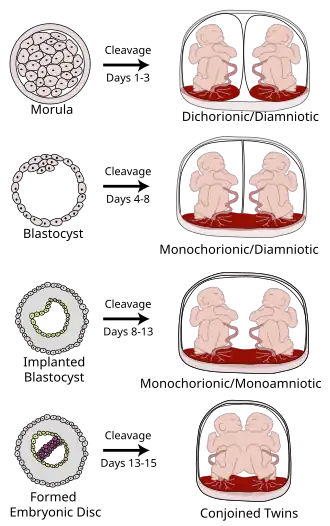

Placentation in the human resulting from cleavage at various gestational ages | |

In the case of twins, dichorionic placentation refers to the presence of two placentas (in all dizygotic and some monozygotic twins). Monochorionic placentation occurs when monozygotic twins develop with only one placenta and bears a higher risk of complications during pregnancy. Abnormal placentation can lead to an early termination of pregnancy, for example in pre-eclampsia.